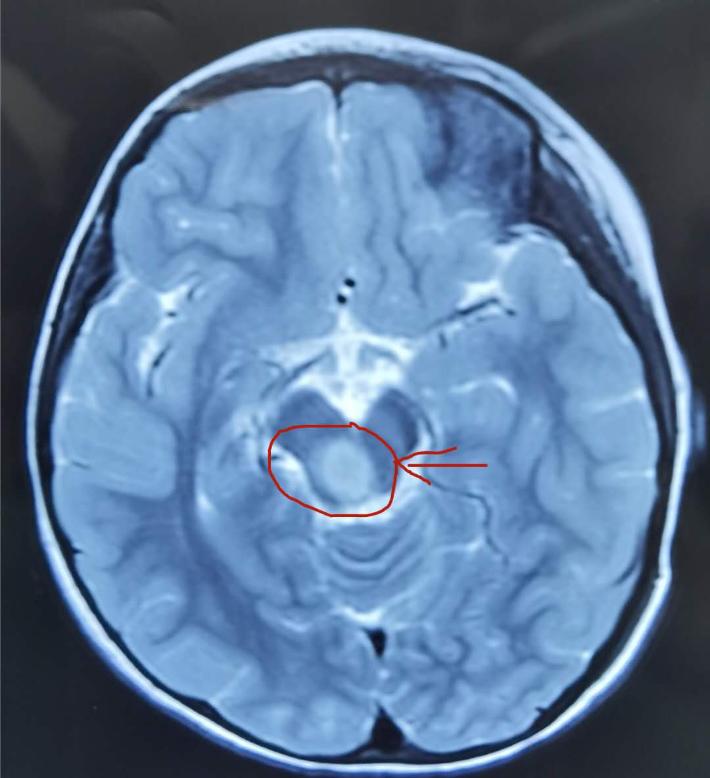

术前轴位

术前轴位,可见肿瘤,用来对比术后轴位